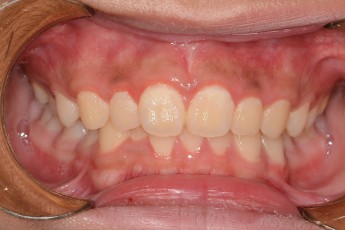

BEFORE & AFTER